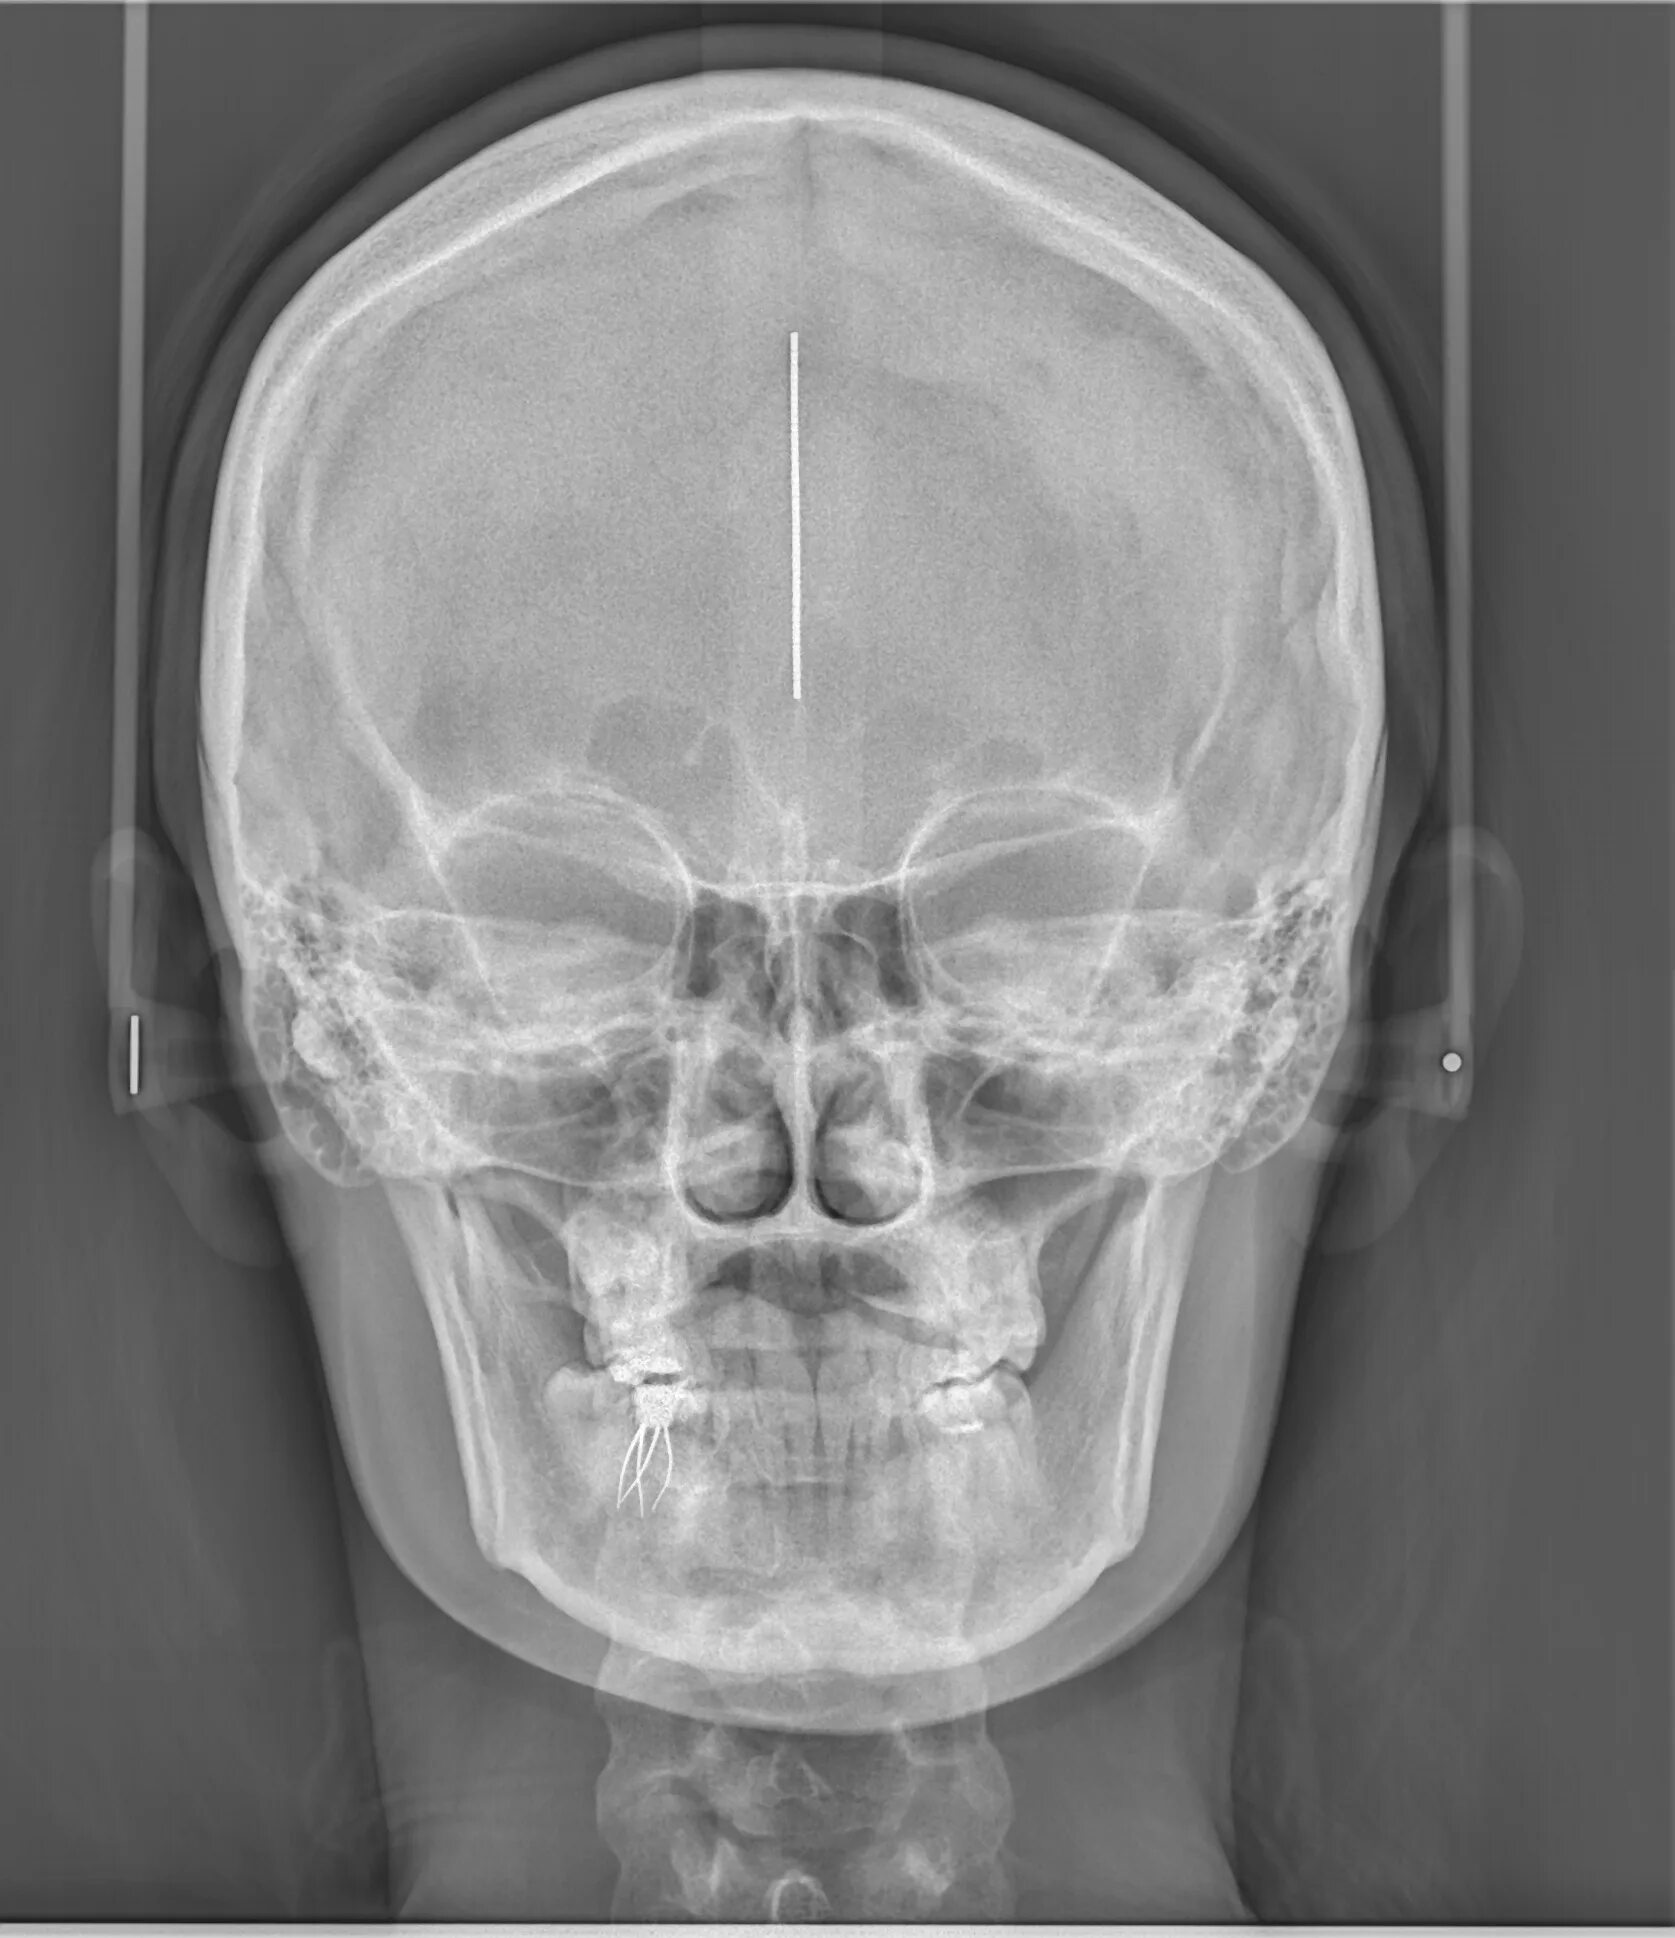

Проекции рентгенограмм черепа